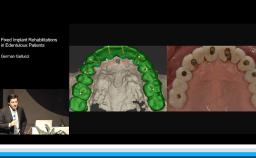

This lecture addresses role of digital imaging in restorative dentistry and discusses its use in facial, dentolabial, phonetic, and dental analysis. This presentation demonstrates the use of imported digital images, an iPad, and the free application iDraw for step-by-step facial analysis of a patient. The lecturer then demonstrates, the design of the smile line, first on the computer and then clinically. Transformation of 2D digital images to 3D images using the DSD Connect software is described. The lecture concludes with a clinical case carried out digitally from start to finish using intraoral scans and CBCT for implant planning and guided surgery.

apply digital imaging in restorative dental practice using available software applications